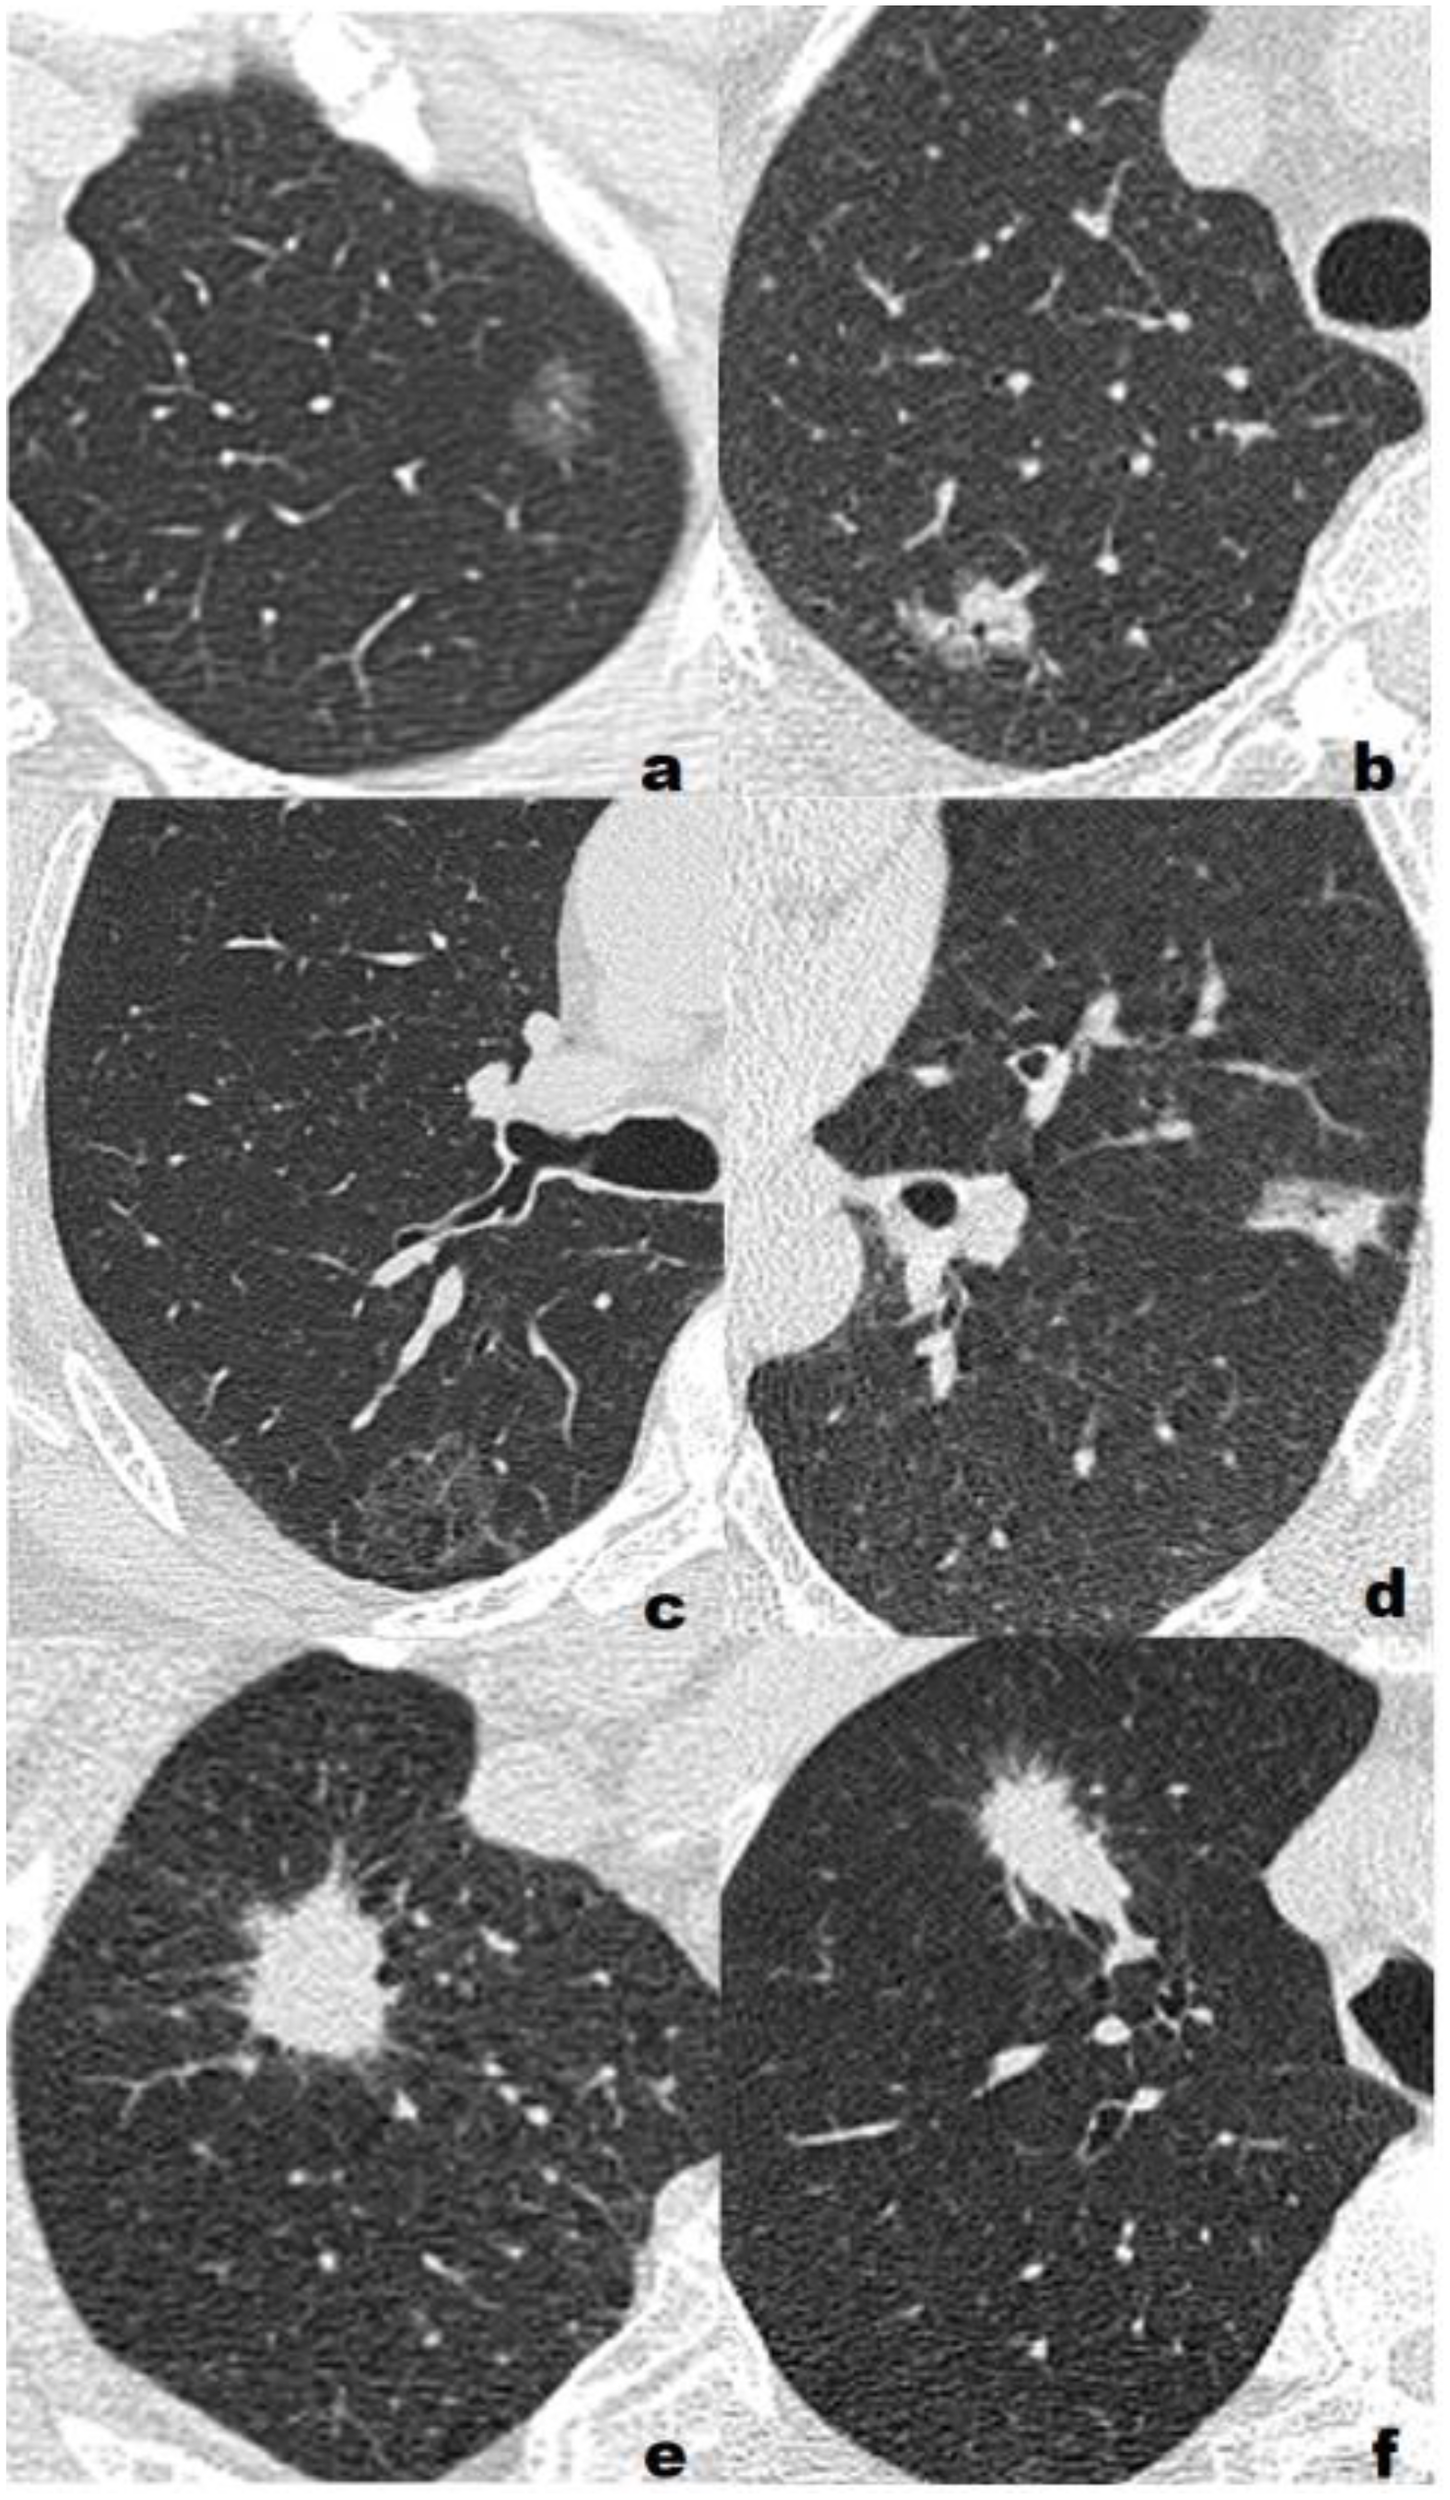

Figure 2

Representative cases of three different pathological grades. (A) Low grade, F, 55Y, T1b, a 1.16-cm lepidic predominant adenocarcinoma with no high-grade patterns in the left upper lobe(LUL) manifesting as a pure ground glass nodule(pGGN). All three model classified the lesion as low/intermediate-grade group; (B) Low grade, F, 72Y, T1b, a 1.64-cm lepidic predominant adenocarcinoma with 5% high-grade patterns in the right upper lobe(RUL) manifesting as a sub-solid nodule(SSN). All three model classified the lesion as low/intermediate-grade group; (C) Intermediate-grade, M, 57Y, T1c, a 2.59-cm papillary predominant adenocarcinoma with no high-grade pattern in the right upper lobe(RUL) manifesting as a pure ground glass nodule(pGGN). All three model classified the lesion as low/intermediate-grade group; (D) Intermediate-grade, M, 61Y, T1b, a 1.73-cm acinar predominant adenocarcinoma with 3% high-grade patterns in the left upper lobe(LUL) manifesting as a sub-solid nodule(SSN). CRM and CRRM classified the lesion as low/intermediate-grade group, RM classified the lesion as high-grade group; (E) High-grade, M, 63Y, T1c, a 2.45-cm acinar predominant adenocarcinoma with 20% high-grade patterns in the right upper lobe(RUL) manifesting as a solid nodule (SN). RM and CRRM classified the lesion as high-grade group, CRM classified the lesion as low/intermediate-grade group; (F) High-grade, M, 73Y, T1c, a 2.85-cm solid predominant adenocarcinoma with 80% high-grade patterns in the right upper lobe(RUL) manifesting as a solid nodule (SN). RM and CRRM classified the lesion as high-grade group, CRM classified the lesion as low/intermediate-grade group.